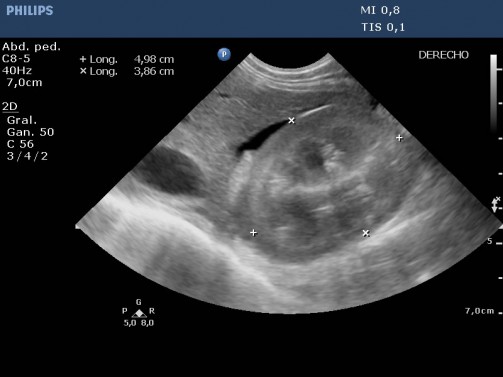

Imagen 1 – Se observa el riñón derecho con volumen y estructura econormales. Además se observa lóbulo hepático y entre ambos la existencia de líquido libre anecogénico (ascitis).